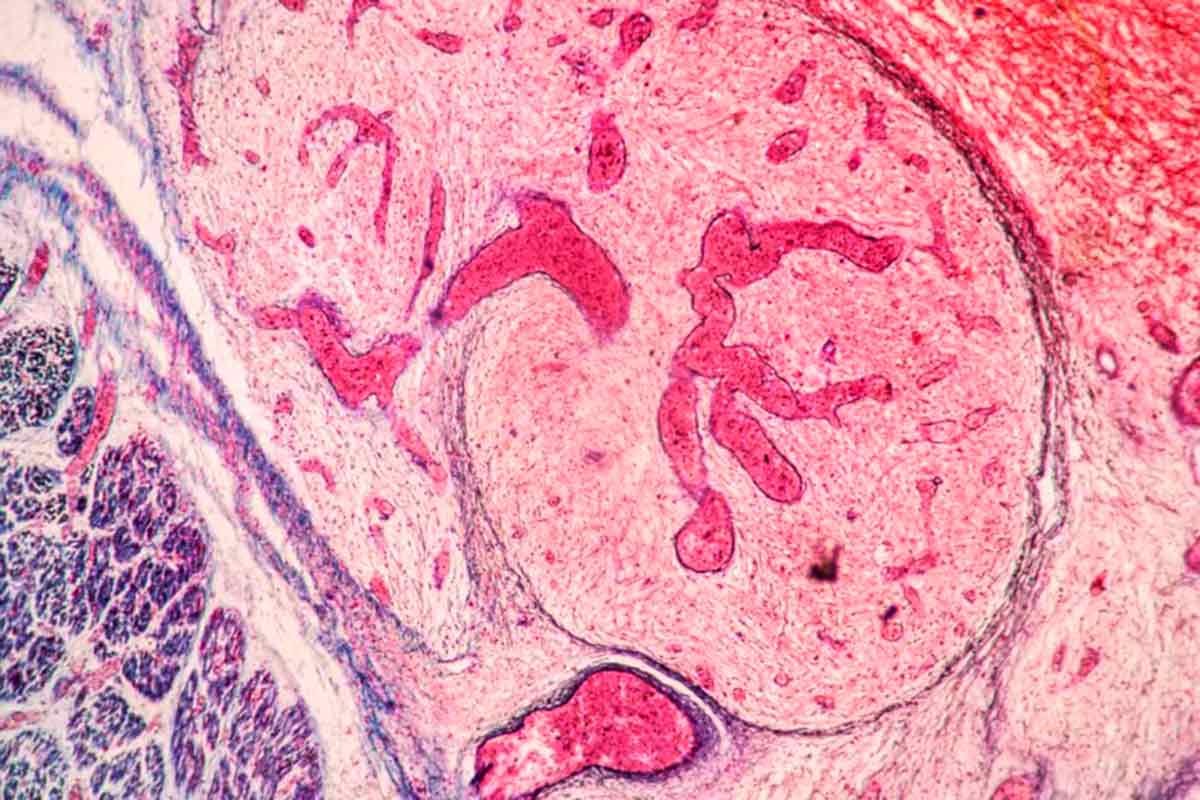

Hoje, para responder a essa pergunta durante a cirurgia, os hospitais utilizam o chamado exame de congelação, considerado o padrão-ouro da patologia.

Nesse procedimento, o cirurgião remove um pequeno pedaço do tecido suspeito e o envia para o laboratório, onde o material é congelado, cortado em lâminas finas e analisado ao microscópio.

Procedimento padrão-ouro atualmente envolve anatomia patológica de tecidos durante a cirurgia — Foto: Adobestock